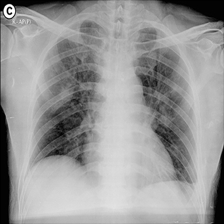

The two infected regions are symmetric.

Fig. 7: Medical image segmentation from QaTa-COV19 dataset. The text annotations are created by hand-craft.

QaTa-COV19: This dataset from Tampere University and Qatar University contains 121,378121378121,378 chest X-ray images (CXRs), including 9258 coronavirus disease 2019 (COVID-19) samples. Each image has a corresponding ground-truth mask for COVID-19 pneumonia segmentation. We choose 50 images as our training set and 10 images as our testing set. In addition, we create the text annotations for this datasets.

Fig. 7 shows the results obtained from experiments on the QaTa-COV19 datasets. Closer inspection of the figure shows that MedT has superiority in depicting long-range information. This benefits from the gated parameters. They can control the amount of information that the positional embedding supplies to key, query and value. It is noteworthy that its ability to learn the local features can still be enhanced.

GTUNet still has trouble capturing local features and depicting the exact edge shape. Inferior to GTUNet, SwinUNet can only produce rough infected regions. However, as shown in Fig. 7, it struggles to catch local details, so some incorrect areas are delineated, and the edge depiction is coarse.

UCTransNet and LViT increase their segmented accuracy. We can observe that they depict the correct infected regions of the first and second IMGs in Fig. 7. What stands out in their result pictures is that they cannot give precise edge information.

Compared with other networks, our model integrates Transformer and CNN into PPE, which ensures that it can obtain meaningful representations. After it has these powerful abilities, we combine PPE and the downstream segmentation tasks. Owing to the pretrained phase and the well-designed decoder, our model presents the most exact segmented results.